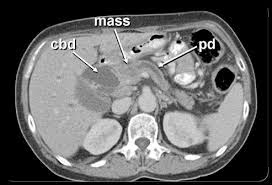

Η προέλευση της πλειοψηφίας των κακοήθων νεοπλασμάτων (95%) προέρχεται από την εξωκρινή μοίρα του οργάνου και διακρίνονται σε αδενοκαρκινώματα, κυσταδενοκαρκινώματα και λοβιακά. Το υπόλοιπο 5% των κακοηθειών προέρχεται από την ενδοκρινή μοίρα του οργάνου. Από τα νεοπλάσματα της εξωκρινούς μοίρας το 90% είναι αδενοκαρκινώματα και συνηθέστερα εντοπίζονται στην κεφαλή ενώ λιγότερο συχνά έχουν εντόπιση στο σώμα και στην ουρά.

• O καρκίνος του παγκρέατος μπορεί επίσης να ανακαλυφτεί με μεταστάσεις, ειδικά του ήπατος, μερικές φορές επώδυνες, μερικές φορές σε ένα πλαίσιο συνολικής αλλαγής της γενικής κατάστασης. Η παρουσία ενός όγκου του παγκρέατος είναι συνήθως εμφανής με εξετάσεις απεικόνισης αλλά είναι επιβεβλημένη η ιστολογική επιβεβαίωση για να προσαρμοστεί το χημειοθεραπευτικό σχήμα φαρμάκων. Η βιοψία μπορεί να γίνει είτε με υπερηχογράφημα, είτε με αξονική τομογραφία είτε με ενδοσκοπικό υπερηχογράφημα.